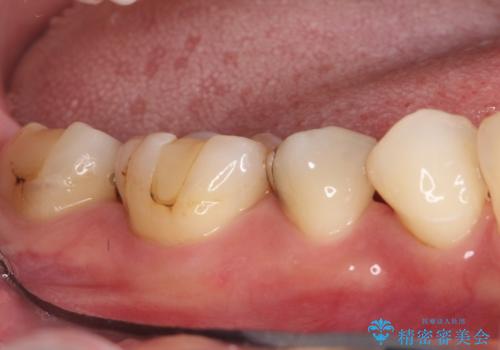

保険診療のCRインレーをセラミックインレーでやり直し

- 定期検診にて他院で治療された保険適用CRインレー部分(大臼歯2本)にむし歯を認めたため、セラミックインレーにて修復を行いました。

e-max プレスインレーにて修復治療を行っているため適合性及び審美性の高い治療を行うことができます